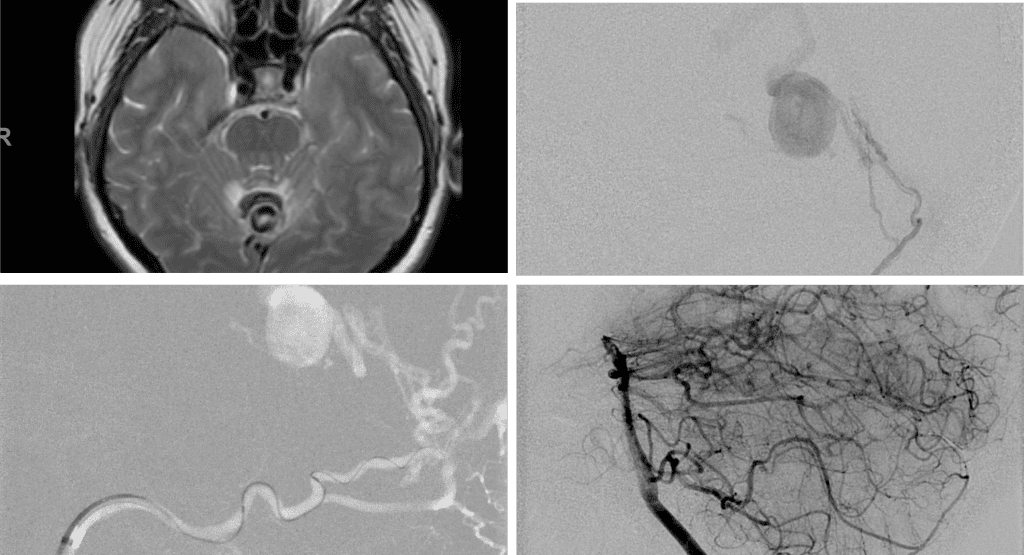

A 55-year-old woman presented with acute onset of severe headache, and possible witnessed seizure. Imaging confirmed intraventricular hemorrhage primarily focused within the fourth ventricle with diffuse subarachnoid hemorrhage within the posterior fossa and along the tentorium as observed on non-contrast CT and MRI of the Brain (Figure 1).

No severe neurologic deficits were observed initially. Her cerebral angiogram revealed a high flow Dural arterial venous fistulous malformation of the tentorium supplied by the bilateral external carotid and left vertebral arteries into a large venous varix within the fourth ventricle at the site of the hemorrhage. Deep venous drainage is observed into the Galenic and Straight Sinus of the posterior fossa (Figure 2).

Figure 2. [A] Ruptured Varix/Aneurysm of the Deep Venous Posterior Fossa drainage and AV shunting (arrows) [B] Posterior Meningeal Artery Fistula [C] Right Middle Meningeal Artery Fistula [D] Post embolization Left Vertebral Angiogram demonstrates resolution of the high flow and pressure A-V Shunting following successful embolization with liquid embolic (NBCA).